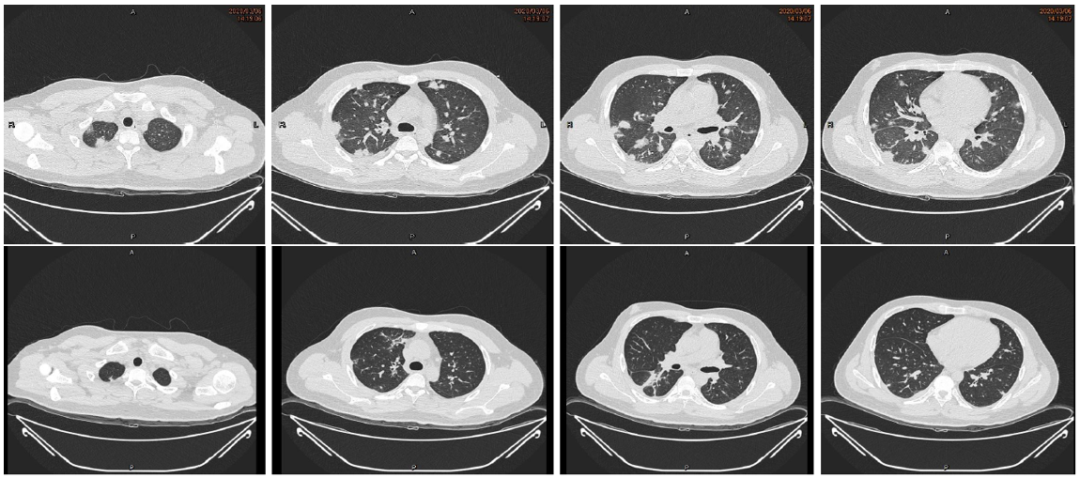

我院23岁男性患者,化脓性扁桃体炎+颈静脉血栓+肺脓肿,抗感染治疗2月余,病灶逐渐消失。

图片